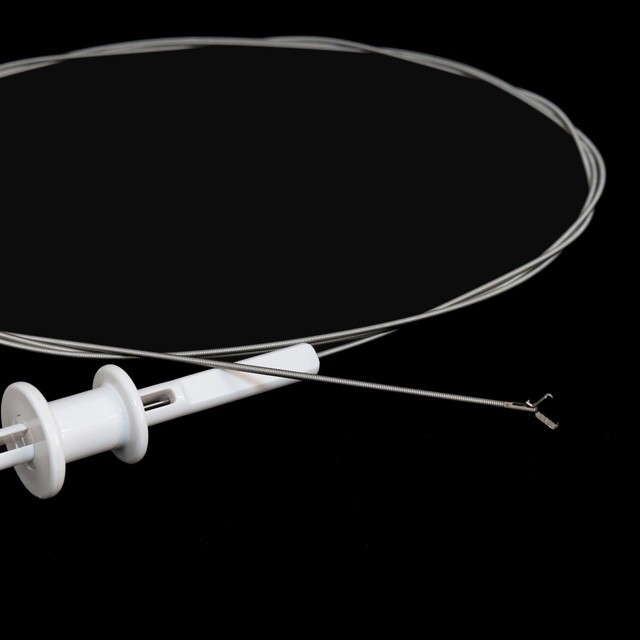

● To maszina je połōnczōno ze yndoskopym do wydobycio i usuwanio cudzyj ciała w przewodze trowiynnym.

● To yndoskopowe norzyńdzie wyszukowanio je wykōnane ze stali niyrościejōncyj do elastycznego stopnia chirurgicznego, co sōm zgodliwe z miyndzynorodowymi certyfikacyjami biospōłczynności dlo bezpiecznego interakcyje pacjynta.}

●Je to precyzyjny mechanizm chwytanio powierzchniowy posiado lyczynie powierzchniowe, co zapewnio minimalne abrazyjo do ôdpornego szlakōw yndoskopicznych w czasie ôperacyje..

● Maszina zawiyro innowacyjny systym stabilizacyje wieloarmowyj zaprojektowany ze materyjami aer i kosmicznym, co zapewnio wyjōntkowy ôdporność na moment ôdciōnganio i akuratność kōntrole dlo bezpiecznego ekstrakcyje zagranicznego ôbiektu.

●Steril pakiet, dispoodalny .

FG-28K-A5 |

2.3 |

Srogsze aniżeli abo rōwne 2,8 |

1600 |

Ja |

Wilgogōwka |

FG-28K-A7 |

2.3 |

Srogsze aniżeli abo rōwne 2,8 |

1600 |

Ja |

Zymb ôd zymba z aligatorym |

FG-28K-A8 |

2.3 |

Srogsze aniżeli abo rōwne 2,8 |

1600 |

Ja |

Pelian |